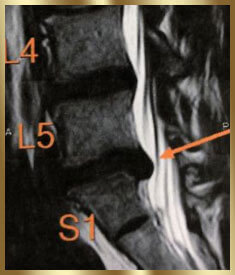

病院では椎間板ヘルニアと

診断された。

重度の椎間板ヘルニアで悩んでいました。どこに行っても治らず、整形外科で神経ブロック注射を2回打っても改善の兆しはなし。

あきらめ半分で手術の専門病院に足を運ぶと…レントゲンとMRIの検査だけで「ヘルニアがあるから手術ね」と告げられてしまったんです。

私の身体に触れもせずあっさり手術宣告(しかも、手術費用は150万円)されてしまい、手術しなくてもいい道を探してたどり着きました。